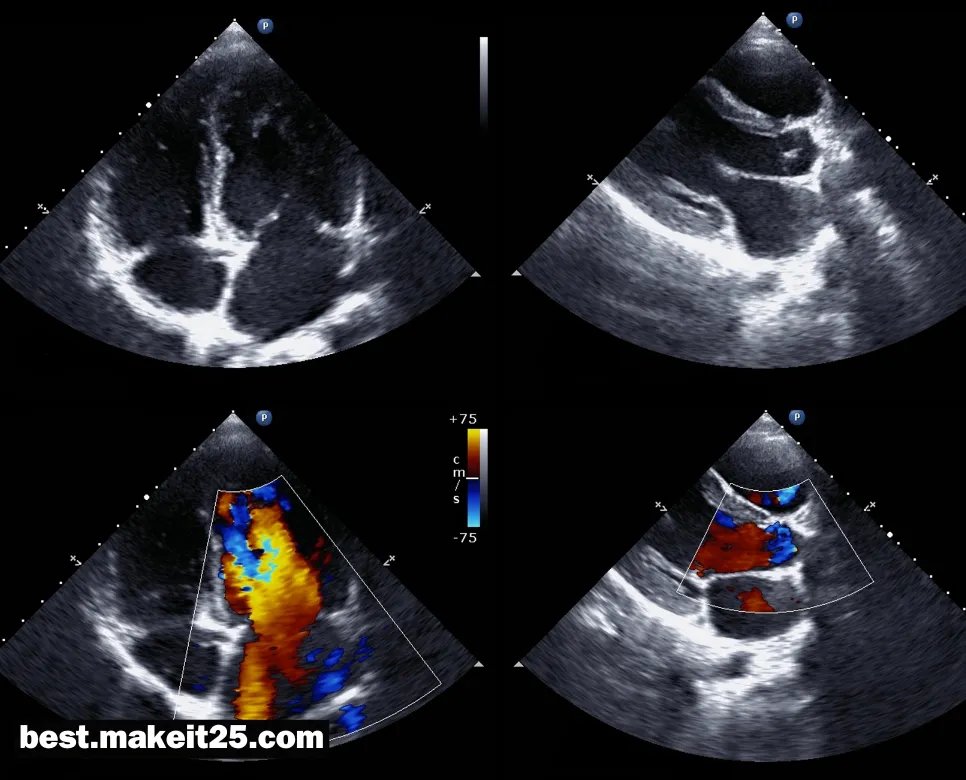

TTE(경흉부 심초음파검사)

TTE는 “Transthoracic Echocardiography”의 약자로, 한국어로는 “경흉부 심초음파검사”를 의미합니다. 이는 흉벽을 통해 초음파를 보내어 심장의 구조와 기능을 평가하는 비침습적인 영상 검사 방법입니다. TTE는 심장 질환의 진단, 심장 기능의 평가, 심장 수술이나 중재시술 후 추적 관찰 등 다양한 임상 상황에서 널리 활용되며, 심장 초음파 검사의 가장 기본적이고 중요한 방법으로 인정받고 있습니다

- 심장 판막 질환: 승모판, 대동맥판, 삼첨판 등 심장 판막의 구조와 기능을 평가하여 협착이나 역류를 진단합니다.

- 심근 질환: 심근경색, 심근병증, 심장 비대 등 심근의 운동과 기능 이상을 평가합니다.

- 관상동맥 질환: 국소 심근 운동 이상을 통해 관상동맥 질환을 시사하는 소견을 확인할 수 있습니다.

- 심부전: 좌심실 구혈률 측정, 심장 내 혈전 유무 확인 등을 통해 심부전의 원인과 중증도를 평가합니다.

- 심장 기형: 선천성 심장 기형의 구조와 혈역학적 영향을 평가합니다.

- 실시간 영상: 심장의 움직임을 실시간으로 관찰할 수 있어 역동적인 평가가 가능합니다.

- 혈역학적 평가: 도플러 기능을 이용하여 심장 내 혈류를 측정하고 판막 역류 등을 정량화할 수 있습니다.